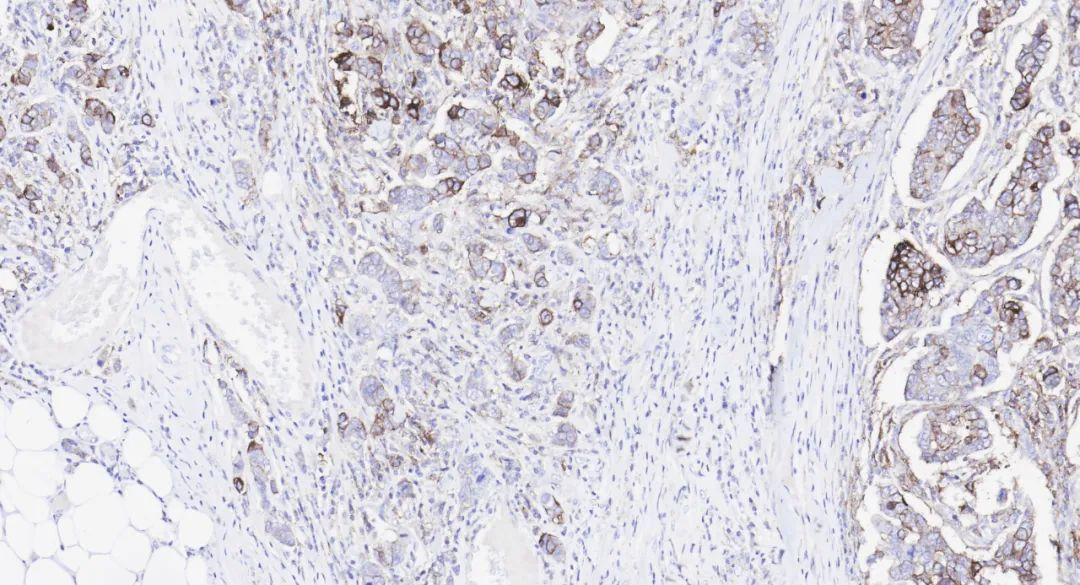

SMH, also known as Myosin (Smooth Muscle) (), is mainly expressed in vascular and visceral smooth muscle cells as well as myoepithelial cells, with occasional expression in myofibroblasts. It aids in the diagnosis and classification of mesenchymal tumors and, and can also be used for detecting breast myoepithelial cells.

carcinoma in situ and invasive carcinomaIn this round of evaluation, a total of152 laboratories participated, with a pass rate of 81% (excellent rate wasIt should be noted that in the past, SMH was limited by antigen retrieval conditions (requiring58%). The focus of the evaluation was on the diagnostic use of SMH in breast samples to distinguish benign and pre-lesions from invasive carcinoma.

Figure 6.trypsin + citric acid high pressure), resulting in poor staining performance on automated platforms. However, Maxin’s SMH (MX109) antibody can now achieve excellent machine staining results under EDTA retrieval conditions.Breast carcinoma in situDual retrieval:

SMH (MX109) staining imageTonsilFigure 7.